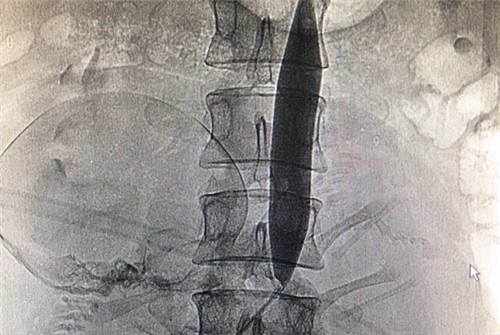

介入科李建国主任与何彤副主任急诊行右股动脉穿刺成功后行腹主动脉造影,经测量分析置入20mm×4cm大球囊,远端定位于髂总动脉分叉上方(L4),在腹主动脉球囊扩张临时阻断下行剖宫产手术。剖宫产手术顺利,胎儿及胎盘娩出后经严密观察子宫切口及阴道无异常出血倾向,顺利关腹并撤出球囊,术中出血量约400ml,产妇及胎儿生命体征平稳,成功保留了患者子宫。手术过程有惊无险,严密有序,通过大家的共同努力手术取得了圆满成功。

球囊阻断低位腹主动脉是腹主动脉阻断术(AAC)的一种,因能有效地预防性控制和减少其阻断平面以下的外科术中致命性大出血,故肿瘤外科、妇产科及骨盆骶尾骨等外科手术得以在基本无血视野下安全地进行手术,由于阻断部位在腹腔干(高位)、肾动脉(中位)、肠系膜下动脉平面下、髂总动脉分叉平面上,既不影响肝肾等重要脏器的血供,又因各动脉分支间存在许多侧支循环通路,不会引起盆腔脏器及下肢缺血等不良后果,近年来被临床外科医生广泛接受。